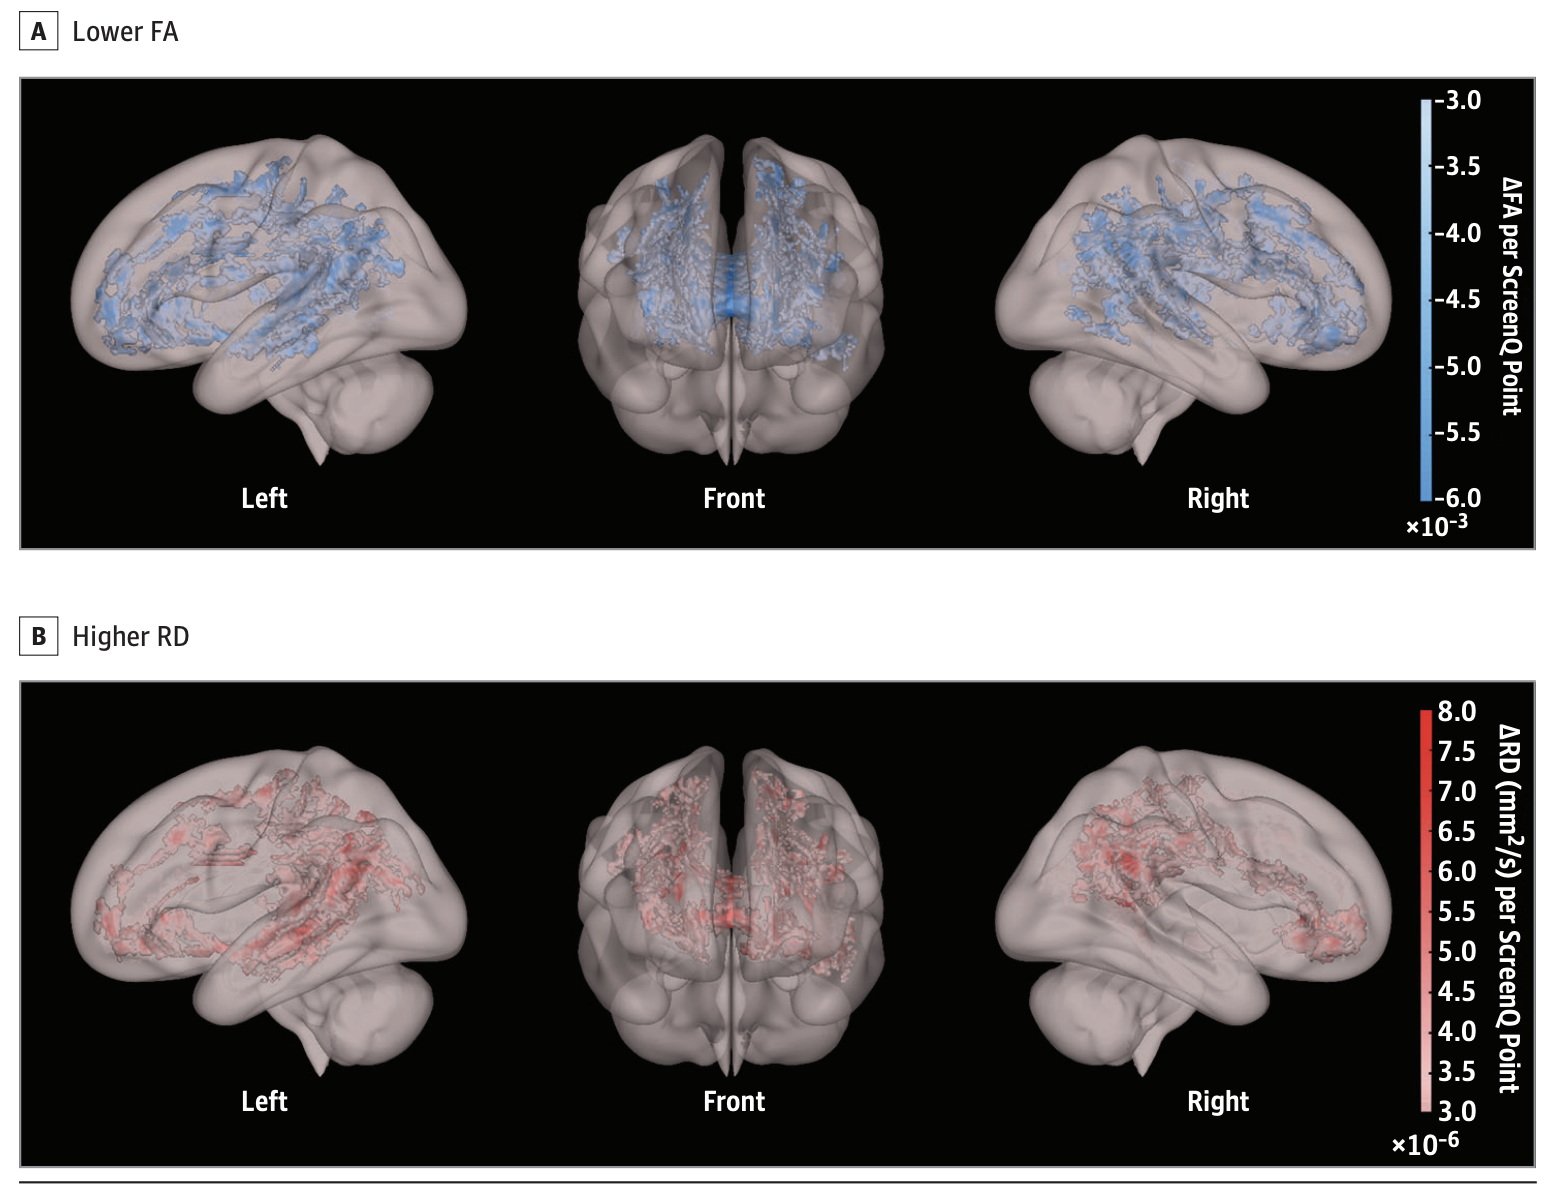

The image includes two panels labeled A and B, with each showing three views of the brain: left, front, and right. These images highlight areas of the brain with altered Fractional Anisotropy (FA) and Radial Diffusivity (RD), which are measurements used in DTI to assess the integrity of white matter (Hutton et al., 2020).

Fractional Anisotropy (FA):

• As a broken down explanation, think of white matter like a bundle of wires. FA tells us how well-organized these wires are. When FA is lower, it's like the wires are fraying or not as neatly lined up, which can mean there's some kind of problem in how brain signals are traveling.

• Lower FA (as shown in panel A) could indicate several things, including loss of fiber tract integrity, demyelination (loss of the protective sheath around axons), or increased membrane permeability. It could be associated with various neurological conditions, normal aging, or even changes due to learning and plasticity.

Radial Diffusivity (RD):

• As a broken down explanation, RD looks at how water moves from one side of the wires to the other. If RD is higher, it's like water can leak out more easily. This might mean that the insulation around the wires (similar to the myelin sheath around axons) is not doing its job properly.

• Higher RD (as shown in panel B) often suggests demyelination, as it means water is more free to diffuse across the axon's normal pathway, which may occur if the myelin sheath is damaged

Results and Interpretations:

• The study found that higher ScreenQ scores, indicating increased screen media use, were correlated with lower FA and higher RD in various white matter tracts of the brain..

• These correlations were particularly prominent in tracts associated with language, executive functions, and emergent literacy skills.

• For example, the arcuate fasciculus, a tract crucial for language processing, showed lower FA and higher RD with increased screen media use. In the brain, the ability to process phonological information is associated with specific regions and pathways, such as the arcuate fasciculus, which connects areas responsible for understanding and producing speech.

• These findings suggest that greater exposure to screen media may be associated with alterations in the micro-structural integrity of white matter tracts important for cognitive functions.

• Essentially, the MRI DTI results indicate that excessive screen media use in preschool-aged children may have adverse effects on the structural development of the brain, particularly in areas critical for language, executive functions, and emergent literacy skills.